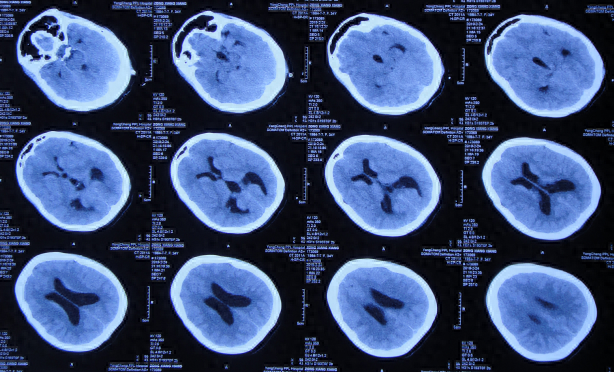

给予甘露醇治疗后10天即2019年2月24日,仍间断头痛和发热,查头颅CT(图-4)后,给予腰椎穿刺术。

图-4:2019年2月24日头颅CT

但腰椎穿刺术后头痛仅短暂缓解1天左右,在该院继续治疗8天,仍间断头痛发热,间断给予腰穿治疗,化验脑脊液白细胞高,曾先后3次查头颅CT(图-5、图-6、图-7)均示脑室并未明显扩张。

图-5:2019年2月26日头颅CT

图-6:2019年2月27日头颅CT

图-7:2019年3月5日头颅CT